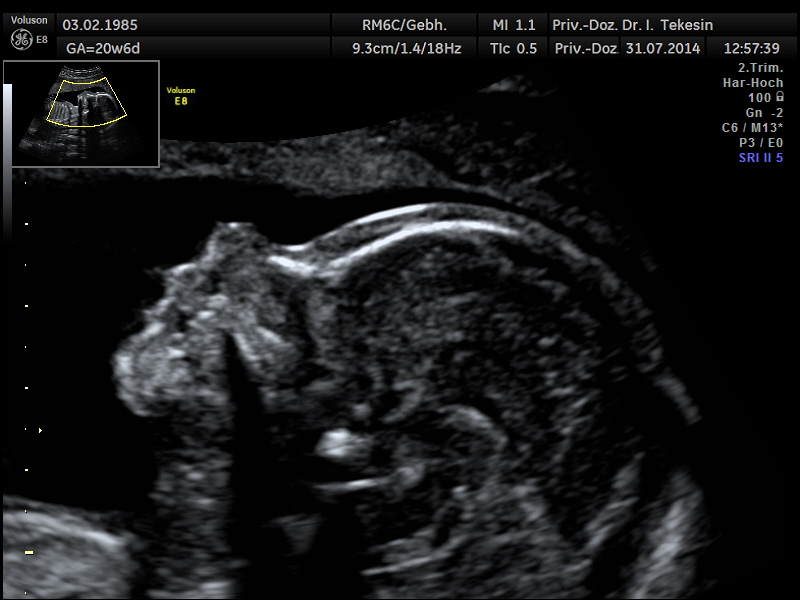

Die Ultraschalluntersuchung ist ein bildgebendes Verfahren, das nach heutigem Kenntnisstand selbst bei wiederholter Anwendung keine Schäden bei Mutter und Kind verursacht. Eine Ultraschallfeindiagnostik können wir Ihnen optimal zwischen der 20. und 22. SSW anbieten.

Eingehende Ultraschalluntersuchung

Diese Untersuchung ist wesentlich umfangreicher als der gemäß den Mutterschaftsrichtlinien vorgesehene Ultraschall in diesem Zeitpunkt. Neben speziellen Geräten erfordert er auch große Erfahrung des Untersuchers.

Entscheidende Rolle bei dieser Untersuchung spielt die Lage des Kindes und die Stärke der mütterlichen Bauchdecken. Dabei betrachten wir alle darstellbaren Organe und Merkmale des Ungeborenen: das altersentsprechende kindliche Wachstum, die Fruchtwassermenge, das Aussehen und die Funktion aller sichtbaren Organe und die Lage und das Aussehen der Plazenta.

Profil in der 21. Woche